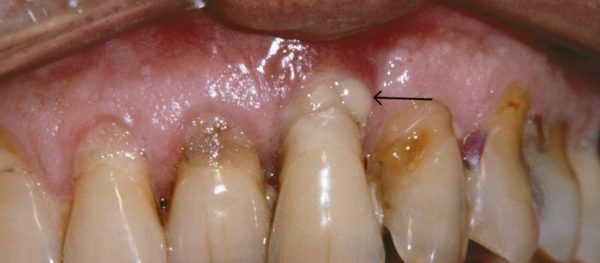

بیماری پریودنتال پیشرفته

مرحله نهایی بیماری پریودنتال یا بیماری پریودنتال نکروز دهنده زمانی اتفاق می افتد که عفونت عمیق تر شود و باکتری ها بار دیگر به باکتری های عامل بیماری تبدیل شوند. بیشتر در افراد مبتلا به بیماری های سیستمیک مانند HIV، سوء تغذیه و سرکوب سیستم ایمنی شایع است. شما اکنون در خطر 50 تا 90 درصد تحلیل استخوان هستید. علاوه بر تحلیل استخوان، بیماری پریودنتال پیشرفته باعث قرمزی لثه های متورم و ترشح چرک، حساسیت به سرما، لق شدن بیشتر دندان ها، جویدن دردناک و بوی بد دهان می شود. مشخصه ویژه آن نکروز (مرگ) بافت لثه، الیاف لیگامان پریودنتال و استخوان های آلوئولار است که باعث بروز ضایعات می شود. این مرحله به جراحی پریودنتال یا لیزر پریودنتال نیاز دارد تا پاکت های عمیق پر از باکتری ایجاد شده را تمیز کند. در صورت عدم درمان، مرحله چهار بیماری پریودنتال منجر به ایجاد فاصله یا شکاف بین دندان ها، تحلیل لثه، نیاز بیماران به دندان مصنوعی دارند و سایر مشکلات کلی سلامتی شود که میتواند جدی باشد.